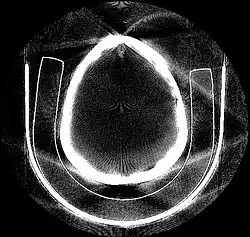

Tomographic reconstruction is a type of multidimensional inverse problem where the challenge is to yield an estimate of a specific system from a finite number of projections. The mathematical basis for tomographic imaging was laid down by Johann Radon. A notable example of applications is the reconstruction of computed tomography (CT) where cross-sectional images of patients are obtained in non-invasive manner. Recent developments have seen the Radon transform and its inverse used for tasks related to realistic object insertion required for testing and evaluating computed tomography use in airport security.[1]